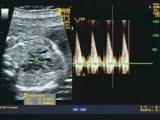

Sospetta stenosi aortica

Ecocardiografia fetale : doppler normale